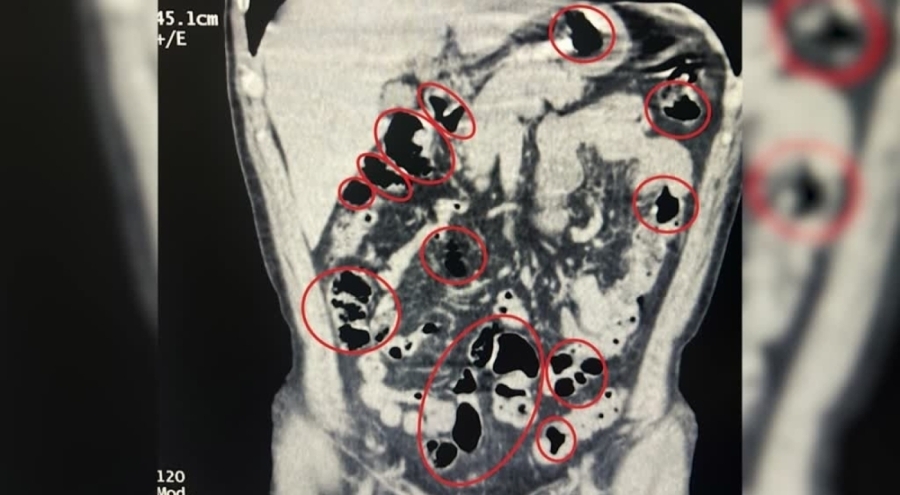

Tatvan'da durdurulan çekicideki kamyonette narkotik dedektör köpeğiyle yapılan aramada 734 gram sentetik uyuşturucu bulundu. Ayrıca, otobüste seyahat eden yabancı uyruklu iki şüphelinin de Tatvan Devlet Hastanesi'nde çekilen röntgen ve tomografilerinde mide ve bağırsaklarında çok sayıda cisim olduğu belirlendi.

Tıbbi müdahale ile çıkarılan şüphelilerin mide ve bağırsaklarındaki 14 kapsül ve üzerlerindeki 36 kapsülde 385 gram sentetik uyuşturucu ele geçirildi.